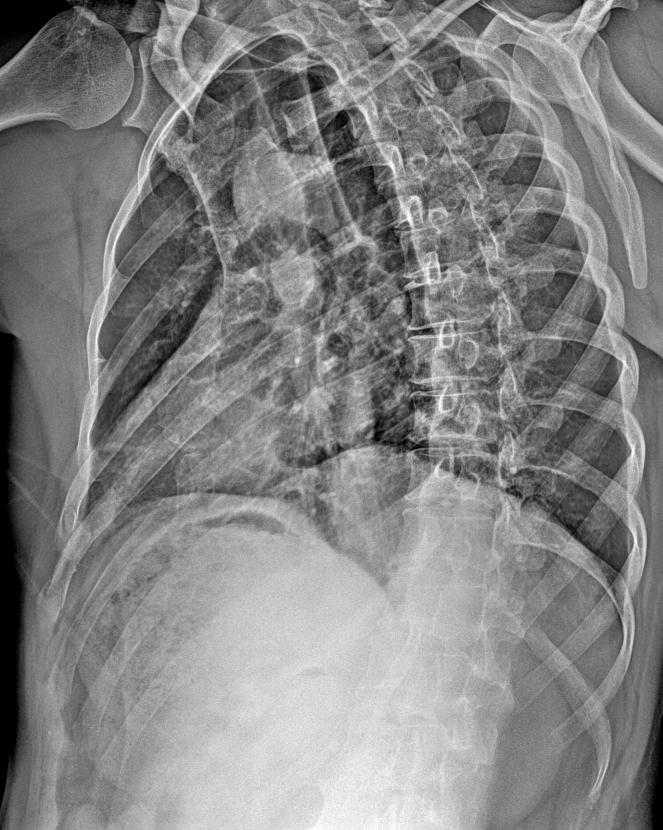

男 45外伤 胸廓正斜位